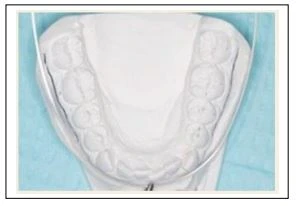

Từ khám lâm sàng lần đầu, ta thấy chen chúc 2mm dẫn đến đưa răng cửa ra trước 1mm. Nếu cung răng dưới có chỗ trống thì sau đó có thể đưa ra sau được. khoảng 2mm sẽ lùi hàm dưới 1mm. Mẫu hàm đuợc dùng để đo chính xác lượng chen chúc trên cung răng. Lượng chen chúc và đưa hàm dưới ra trước của cung răng được chọn sẽ được đo đạc để loại trừ việc đoán. Dùng các số đo chen chúc trên mẫu để xem xét sửa các “vấn đề do không nhổ răng”.